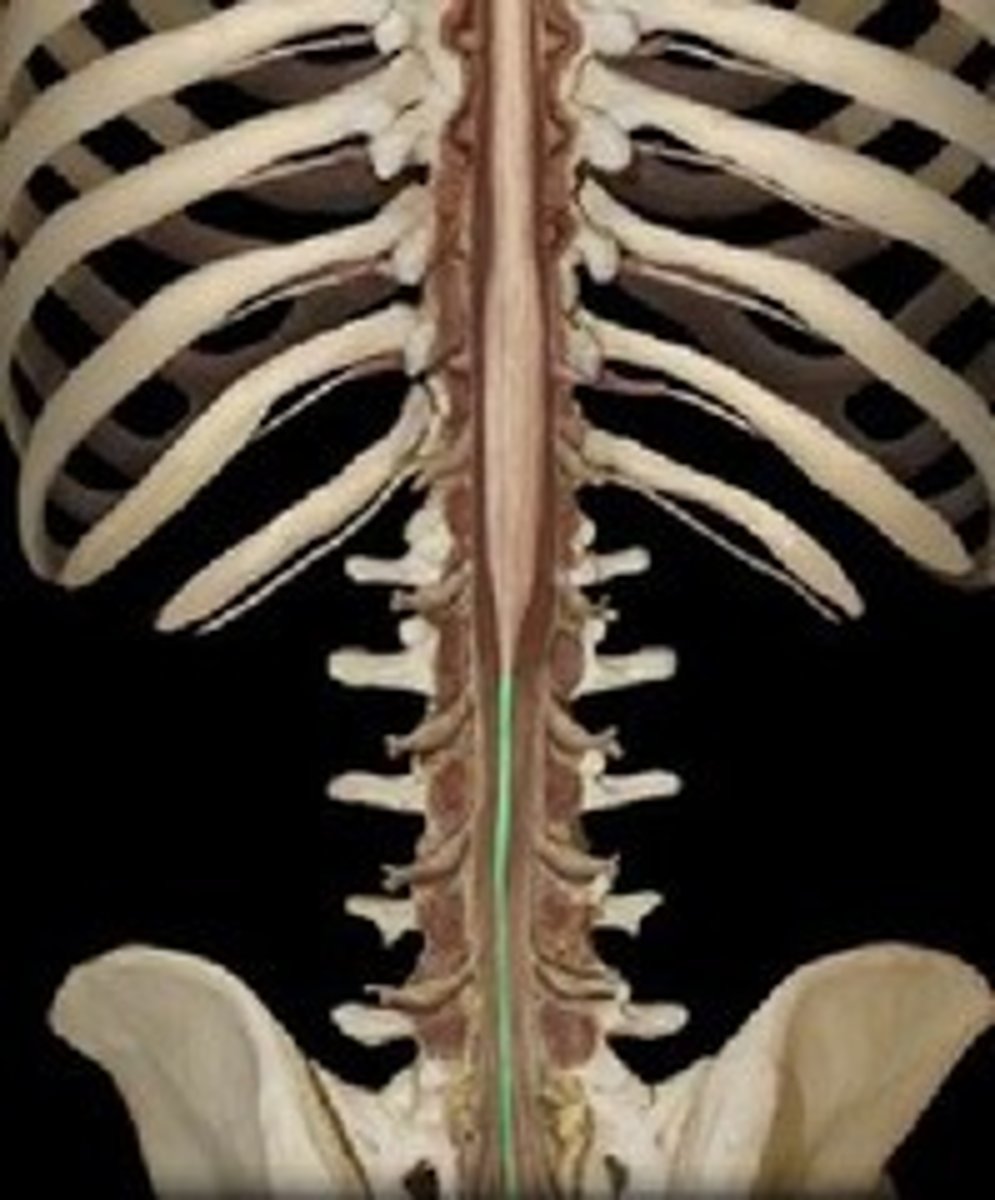

spinal cord

a major part of the central nervous system which conducts sensory and motor nerve impulses to and from the brain; housed within the vertebral canal

cervical region of spinal cord

supplies neck, shoulders, and upper limbs, C1-8

thoracic region of spinal cord

supplies thoracic cage, T1-12

lumbar region of spinal cord

supplies hips & front of lower limbs, L1-5

sacral region of spinal cord

supplies buttock, genitalia, and backs of lower limbs, S1-5

conus medullaris

inferior tapered end of spinal cord

cauda equina

collection of spinal nerves below the end of the spinal cord; below L1 vertebrae

filum terminale

fibrous extension of the pia mater; anchors the spinal cord to the coccyx